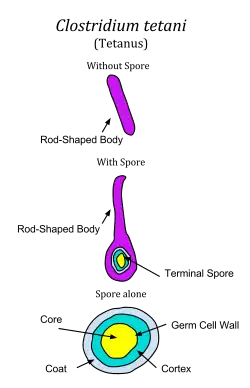

Tetanus is caused by the tetanus bacterium, Clostridium tetani.[1] The disease is an international health problem, as C. tetani endospores are ubiquitous. Endospores can be introduced into the body through a puncture wound (penetrating trauma). Due to C. tetani being an anaerobic bacterium, it and its endospores thrive in environments that lack oxygen, such as a puncture wound. With the changes in oxygen levels, the turkey drumstick-shaped endospore can quickly spread.[26]